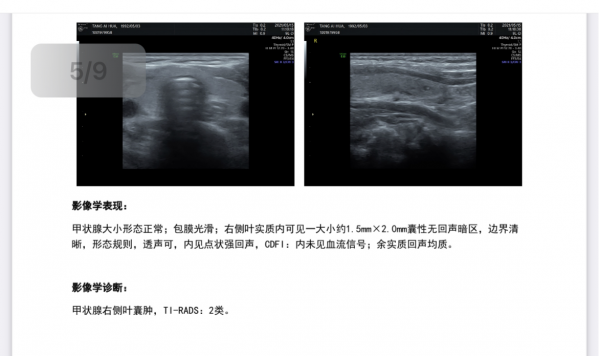

到2021年11月3日六診時,劉女士傳來喜報,彩超複查甲狀腺和乳腺,結節均已消失不見,彩超顯示乳腺、甲狀腺內未見異常回聲。